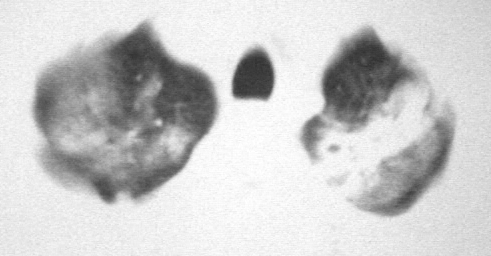

男,36岁,一月前醉酒淋雨后发热咳嗽,气短进行性加重.

抗生素治疗无效,痰检(一).

影像诊断:结核? 还有其他考虑吗?

双肺内中部见略不对称性蝶翼状高密度区,边界不清,部分呈磨玻璃样密度,并可见含气支气管征。肺门、纵隔内未见肿大淋巴结影。无胸腔积液。

考虑:1、肺炎,建议进一步查冷凝集试验除外支原体肺炎;

2、不除外霉菌感染。